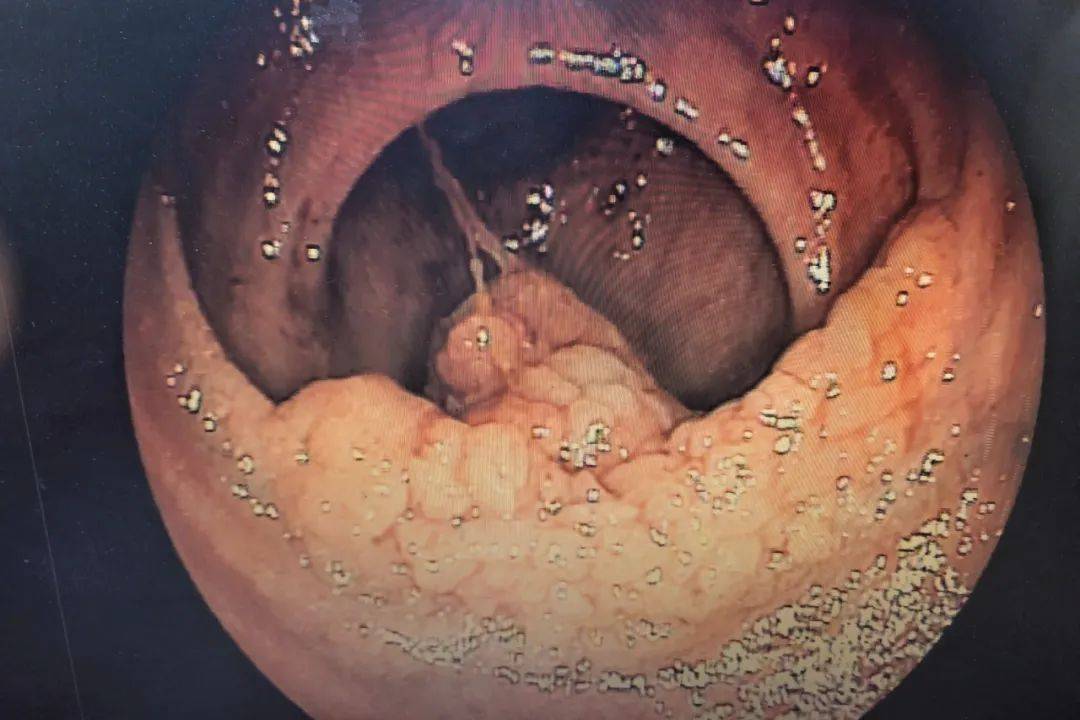

直肠菜花状肿物

结果,不出所料,距肛门17-20cm处,一巨大菜花状占位性肿物,质硬脆,易

行结肠镜检查提示距肛门约15cm有一菜花样肿物,侵及肠腔近半周,活检

结肠镜:菜花样病变,阻塞肠腔.